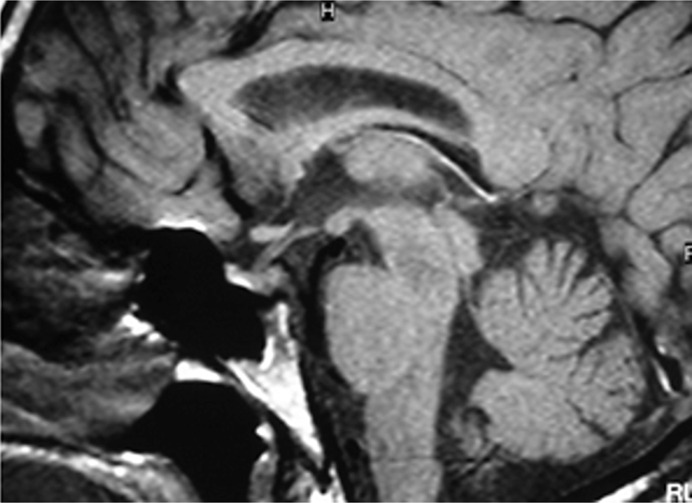

Case presentation: This study describes the clinical features and the genetic analysis of a father and his son with familial CDI. Both presented in childhood with typical symptoms, including polyuria, polydipsia, and hypernatremia. Diagnosis was confirmed through water deprivation testing and subsequently supported by sellar magnetic resonance imaging. Genetic analysis identified the rare germline variant c.329G>A (p.Cys110Tyr) in the AVP gene, in heterozygosity, which segregated in the parent-child pair, thereby elucidating the familial basis of the CDI.